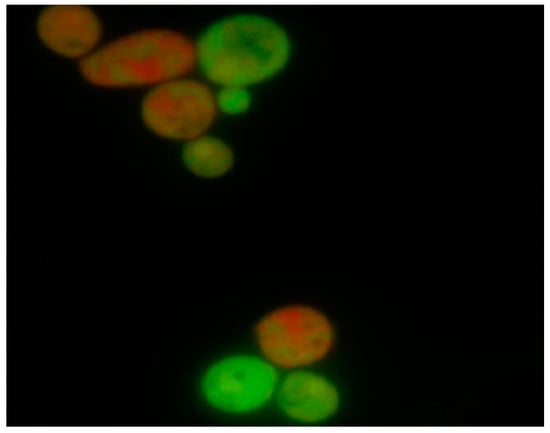

Analysis of C. albicans cells following 18 h in vitro exposure to oleuropein indicated a cytotoxic effect of oleuropein that was concentration-dependent. Further, intergroup comparison of viable vs. dead cells using the Pearson chi-square test revealed statistically significant differences (p < 0.05) between tested concentrations. In the samples treated with concentrations, 1.25 mg·mL−1 and 0.195 mg·mL−1 of oleuropein apoptosis was a predominant type of cell death. Differentiation between viable and dead cells after treatment with the test agent and the altered morphology of the nuclear chromatin visualized by fluorescence microscopy is shown in Figure 1.

Figure 1. Appearance of C. albicans blastospores treated with oleuropein following staining with ethidium bromide and acridine orange according to the fluorescent-dye exclusion method: viable normal blastospores excluded ethidium bromide, and their nuclei were bright green with an intact structure. Non-viable cells had orange to red colored chromatin with organized structure. Apoptotic cells were bright green with highly condensed or fragmented nuclei.